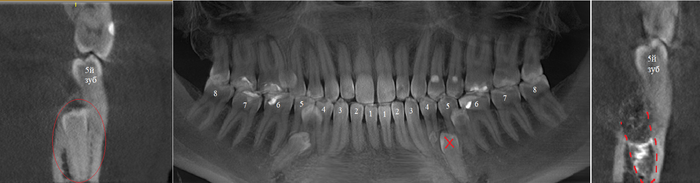

Согласитесь, не особо эстетично. Ортопантомограмма:

Фрагмент компьютерной томографии (вид сбоку):